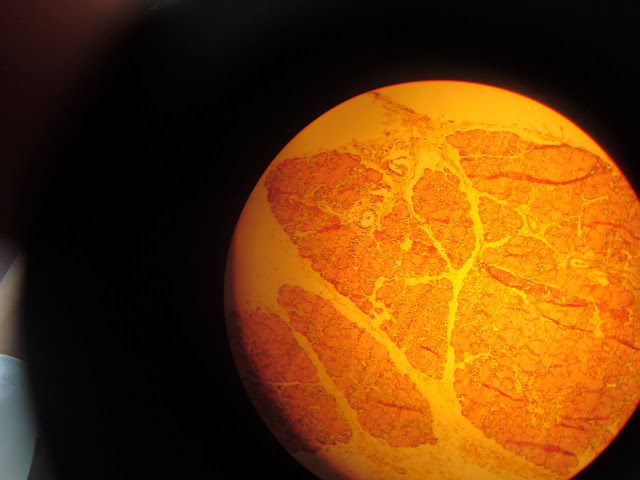

Aquí tenemos otra foto de la glándula submaxliar vista a 100 aumentos (10X). Es un lobulillo se ve el tejido conectivo que lo rodea (cápsula) y acinos más serosos que mucosos.